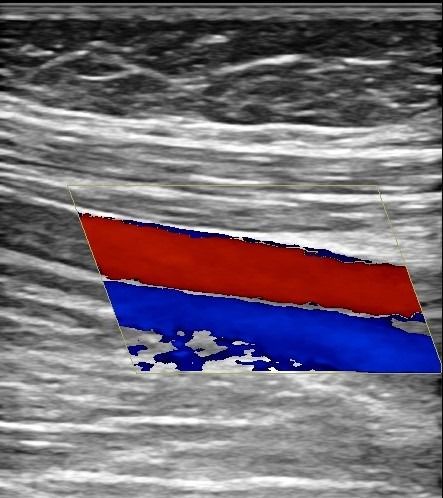

Το Triplex Φλεβών Κάτω Άκρων μας δίνει τη δυνατότητα να εξετάσουμε τις φλέβες με ακρίβεια και αξιοπιστία. Το Triplex μας επιτρέπει να ανιχνεύσουμε περιπτώσεις εν τω βάθει ή επιπολής φλεβοθρόμβωσης και να εξετάσουμε την παρουσία ανεπάρκειας στις φλέβες (κιρσοί).

Με το Triplex Αρτηριών Κάτω Άκρων μπορούμε να αξιολογήσουμε αν υπάρχει παθολογία στις αρτηρίες. Συνήθεις παθολογίες στις αρτηρίες είναι τα ανευρύσματα και οι στενώσεις. Με το Triplex μπορούμε να υπολογίσουμε με ακρίβεια το βαθμό στένωσης στις αρτηρίες και να διαπιστώσουμε αν υπάρχει απόφραξη. Η δυνατότητα διάγνωσης παθολογιών στις αρτηρίες των κάτω άκρων με τη χρήση του Triplex είναι πολύ χρήσιμη για την αντιμετώπιση αγγειακών προβλημάτων, καθώς πρόκειται για παθήσεις που μπορούν να οδηγήσουν σε σοβαρές συνέπειες αν δεν ανιχνευθούν έγκαιρα.